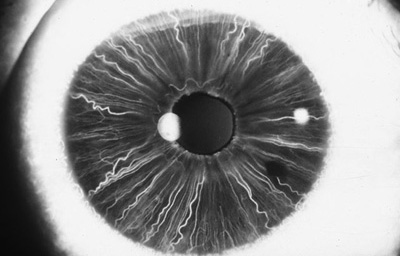

En la cara Posterior se ven pliegues radiales muy finos que se extienden desde el margen pupilar hasta el collarete ( miden ± 1.0 mm), y son conocidos como Pliegues radiales de contracción de Schwalbe. Existen ademas los llamados Pliegues estructurales de Schwalbe que son mas gruesos y mas distanciados en la porción ciliar de la cara posterior

Cara posterior de Iris: incluye Iris y Cuerpo Ciliar, Foto tomada de globo ocular de banco de ojos.